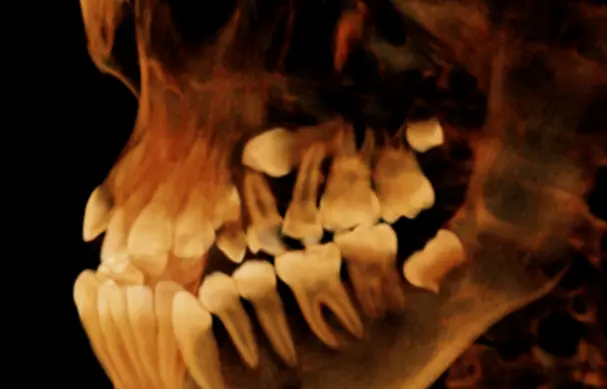

TOMOGRAFÍA DE DIENT​ES RETENIDO

Se da en casos de dientes que no completaron su proceso de erupció​n y su ubicación es compleja.